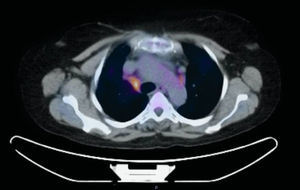

Presentamos el caso de una mujer de 58 años con antecedentes de trombosis venosa profunda subclavio-yugular, en enero de 2014, con tromboembolismo pulmonar secundario e hipertensión pulmonar no estudiada por falta de consentimiento por parte de la paciente, insuficiencia tricuspídea moderada y asma bronquial intermitente. Natural de Marruecos, con último viaje en septiembre de 2013. Vive en ambiente urbano y convive con 2 perros, con adecuado seguimiento veterinario. Ausencia de otros datos epidemiológicos, de antecedentes familiares, de alergias medicamentosas conocidas y de hábitos tóxicos o exposiciones ocupacionales de interés. Acude al servicio de neumología, en febrero de 2015, derivada por su médico de cabecera, debido a un cuadro de 6-8 semanas de evolución, consistente en sensación distérmica con fiebre no termometrada, disnea de medianos esfuerzos, tos con escasa expectoración blanquecina y espesa, hiporexia y astenia. En el examen físico destacó una ligera taquipnea, boca séptica con pérdida de varias piezas dentales, sin aftas, tonos cardiacos rítmicos y sin soplos, y murmullo vesicular globalmente disminuido con crepitantes finos bibasales. Sin otros datos de interés. Las pruebas de laboratorio mostraron un aumento leve de la proteína C-reactiva y una discreta leucocitosis. Sin hallazgos patológicos en muestras de esputo seriadas (baciloscopias y cultivos). La radiografía de tórax mostró una cardiomegalia global y un infiltrado intersticio-alveolar basal derecho. Se realizó tomografía axial computarizada (TAC) de tórax, evidenciándose adenopatías hiliares bilaterales y mediastínicas de tamaño significativo, estas últimas a nivel paratraqueal bajo y subcarinal junto con un infiltrado de características alveolares a nivel del lóbulo inferior derecho. Dados los hallazgos de la TAC, se solicitó la realización de una tomografía por emisión de positrones (PET) y se confirmó el aumento de metabolismo a nivel paratraqueal derecho bajo (standardized uptake value [SUV] de 4,7, fig. 1), hiliar bilateral (SUV de 2,2) y sobre zona de infiltrado alveolar basal derecho (SUV de 2,3), compatible con proceso infeccioso/inflamatorio. Se realizó broncoscopia flexible, sin evidenciarse alteraciones endobronquiales, con resultados microbiológicos y citológicos dentro de la normalidad. Posteriormente se llevó a cabo exploración mediante ecobroncoscopia (EBUS) lineal con adenopatía a nivel 4R de 12mm de eje corto, que se punciona con aguja citológica de 22 G en 3 ocasiones con citopatólogo «in situ», que objetivó la presencia de estructuras ramificadas en parte del material valorado. Se remitieron las muestras obtenidas para su análisis citológico y microbiológico, aislándose en todas las muestras remitidas a microbiología Actinomyces graevenitzii (A. graevenitzii), resistente a ciprofloxacino. Tras tratamiento antibiótico dirigido con amoxicilina-clavulánico y clindamicina se constata mejoría del cuadro clínico.